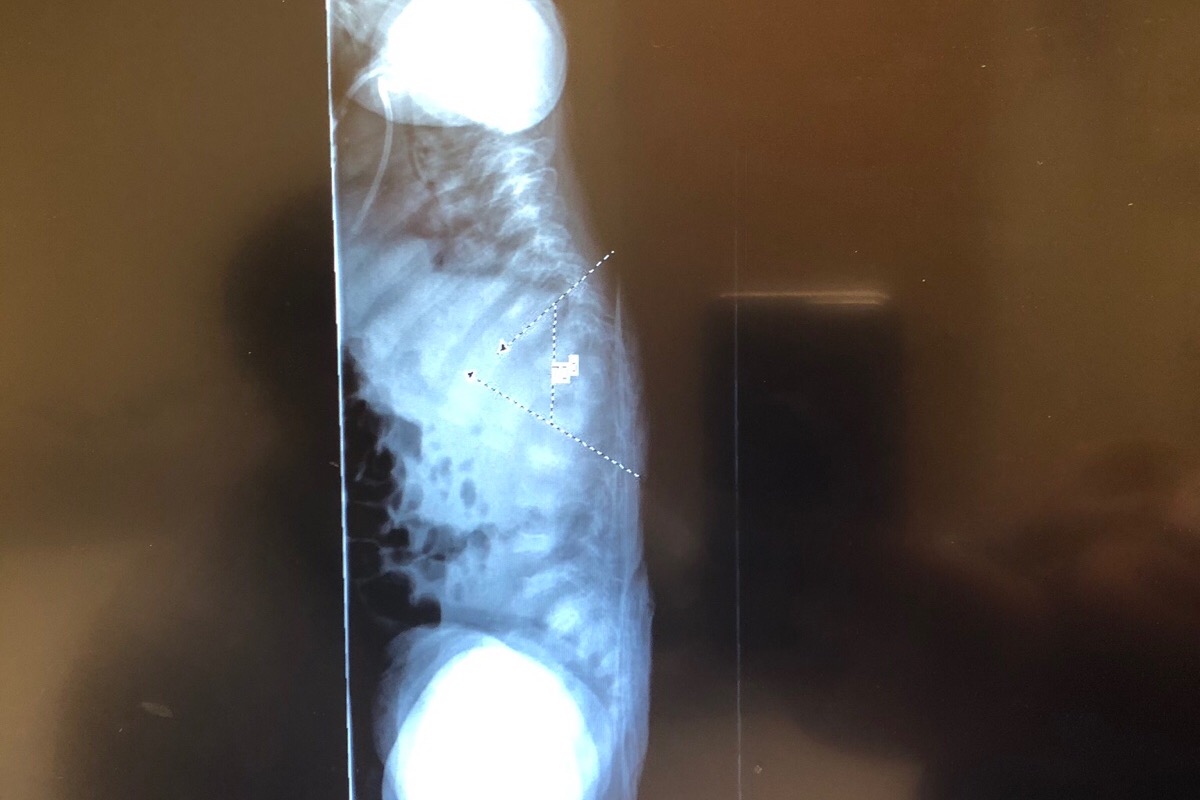

My name is Paola and im Juliet’s mom. Juliet was born September 20,2016. During my pregnancy Juliet’s bones were measuring shorter and they were bowed. The day she was born they immediately rushed her to the NICU due to her not breathing. Later on that day a NICU nurse came to talk to my husband and I and let us know that Juliet had 67 broken bones and they were all in different healing stages and they did not have a reason as to why but if they knew something they would let us know. My husband and I weren’t allowed to hold Juliet until she was about a week old due to her broken bones and not wanting us to cause more. After Juliet being in the NICU for 3 weeks they asked us if we knew what Osteogenesis Imperfecta was and I didn’t even know how to say it so at that point the Dr. told us that she suspected that, that was Juliet’s condition. She contacted a Dr. that specializes in OI and a week later they diagnosed her with type 2 and they let us know that she had already made it 3 weeks and that we don’t know how much longer she was going to live so it was best to take her home to pass away. After 7 weeks we received her genetics report and it turns out she has OI type 8. It’s a really rare type that was just discovered not too long ago. As of today we go along with what Juliet’s body tells us. She will be 3 this year and she has had over 200 fractures in her body. The dr recently decided that Juliet is ready for rodding surgery. First we will start with femurs then we will do Tibias. Hopefully one day Juliet will walk. As you all know anything that involves drs is a lot of money and as much and Juliet’s dad and i want to cover all the expenses it is impossible. The money raised will go towards Juliet’s surgery and wheelchair. We would really appreciate the help and thank you so much ❤️